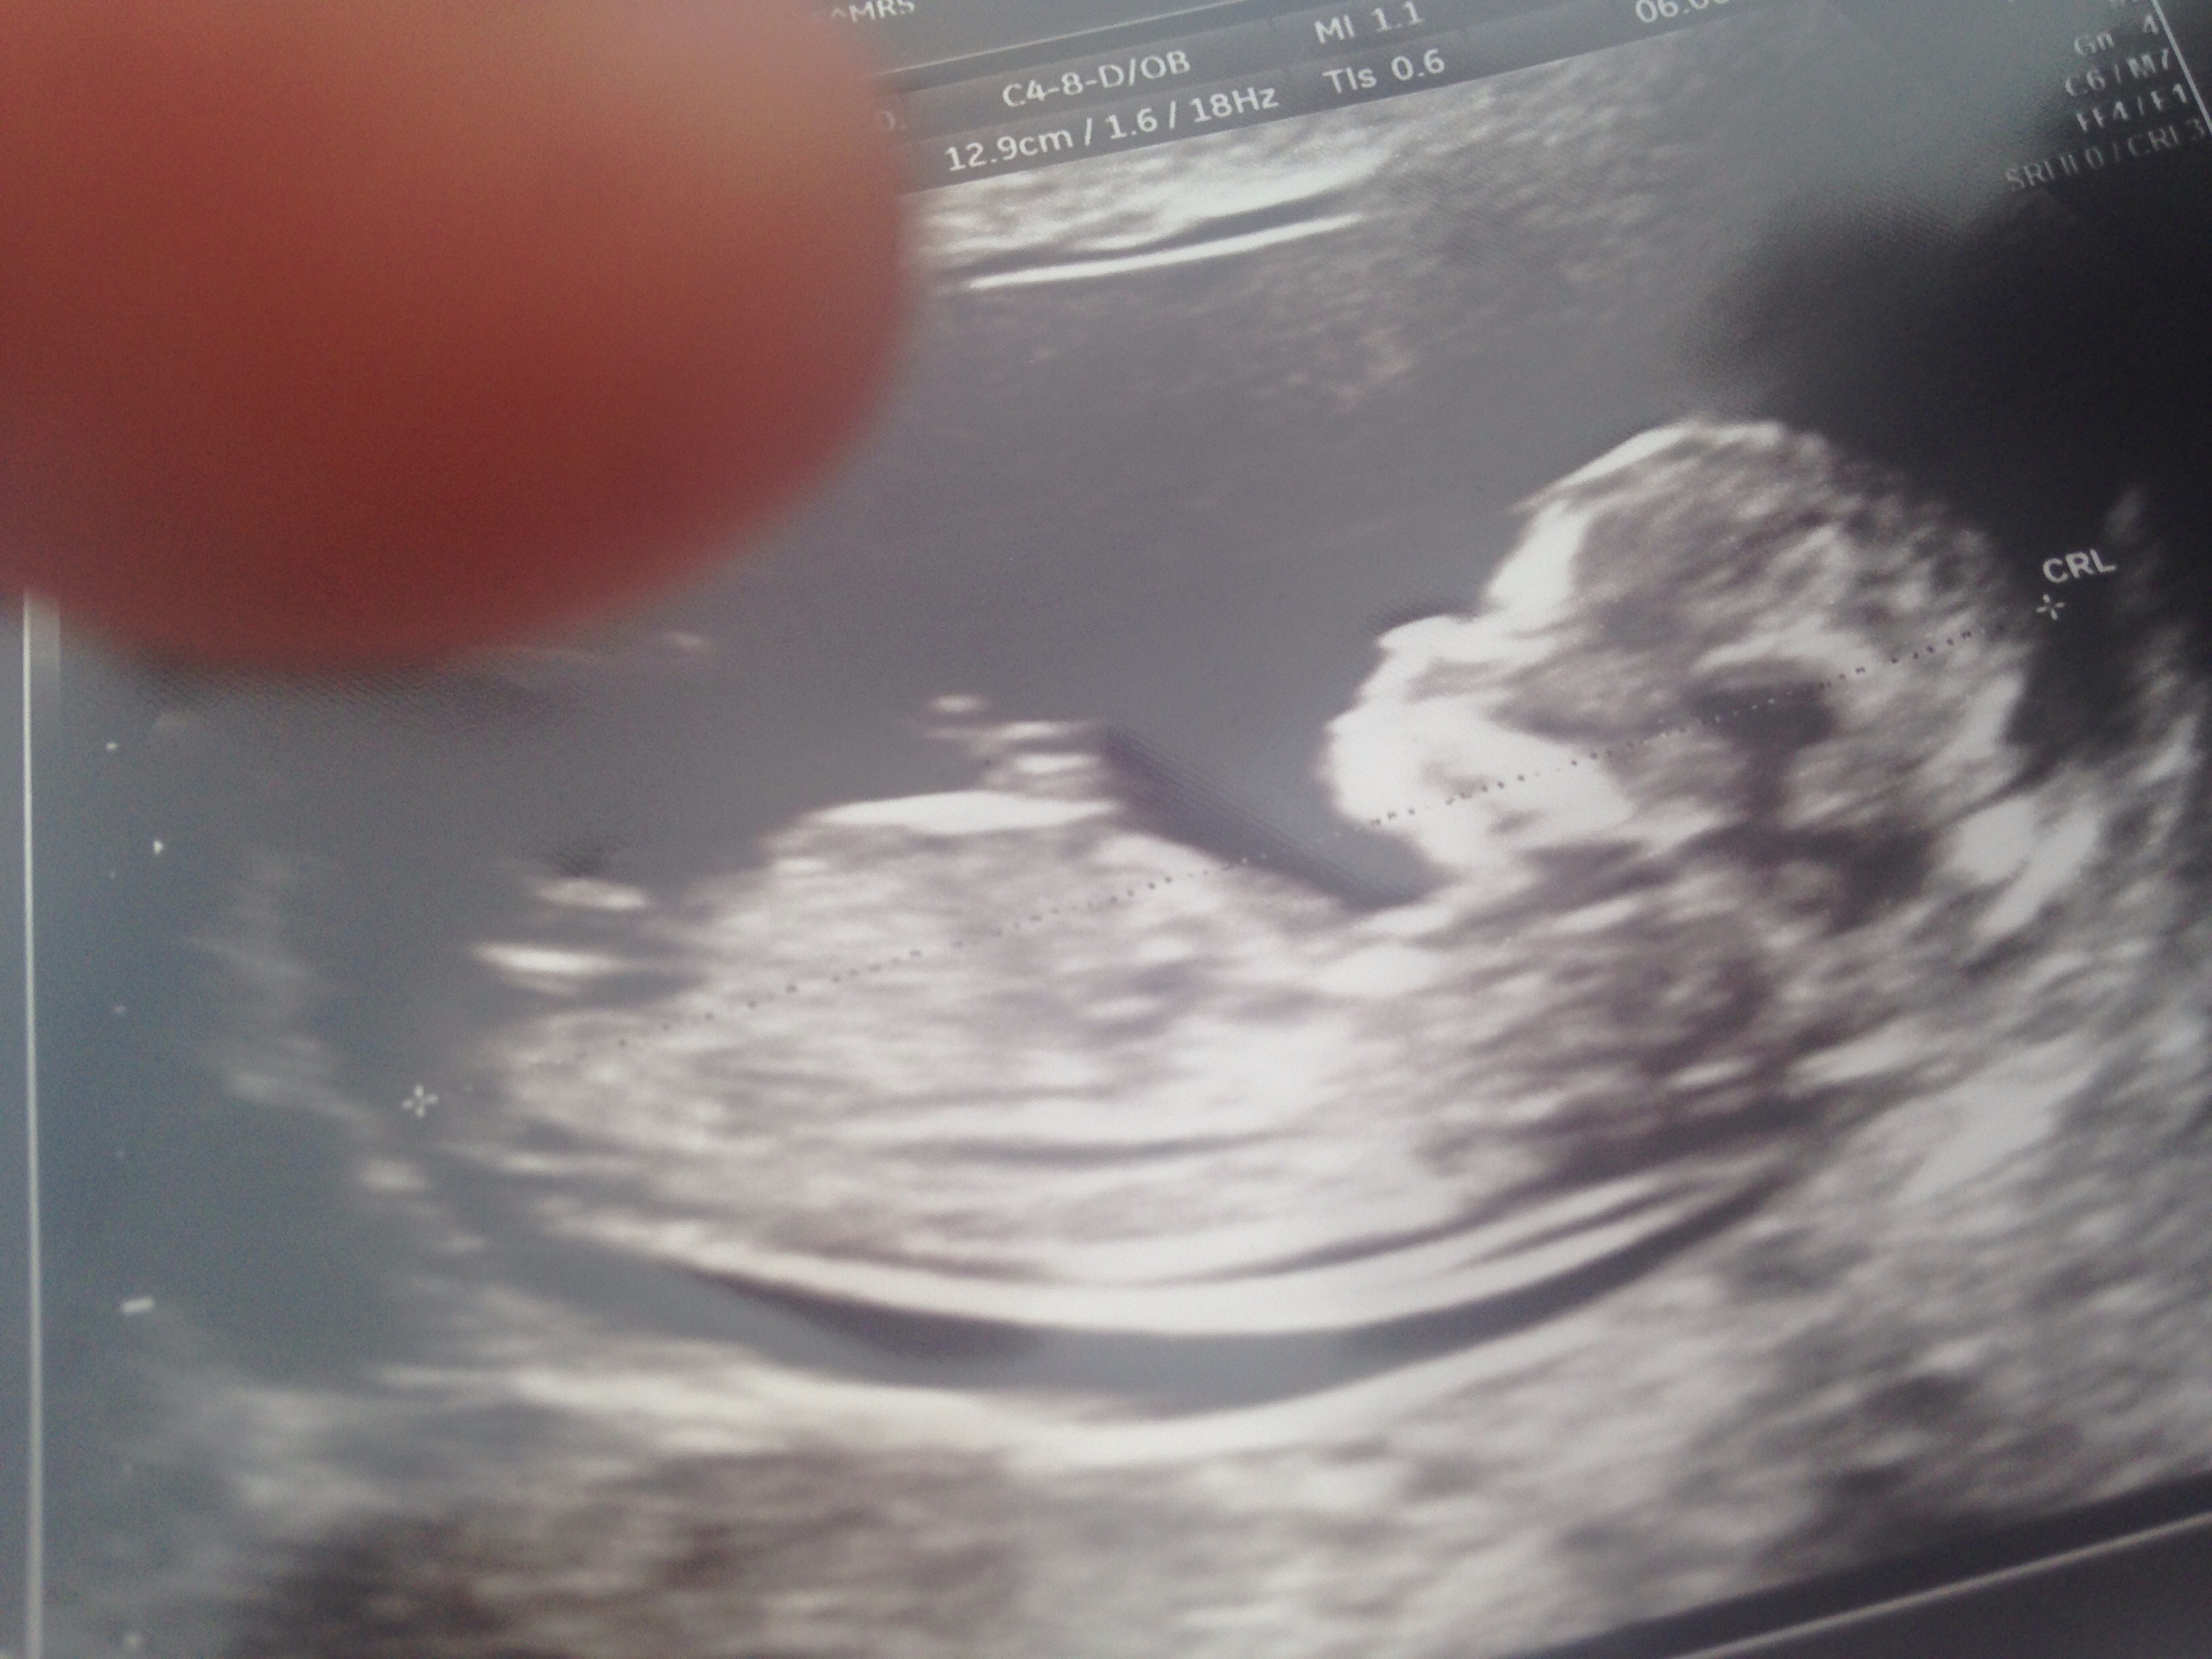

So after my ht journey not working out I am now pregnant naturally !! Scared of Gd but prepared either way!!! Here's my pics !! Attachment 31651Attachment 31652Attachment 31653Attachment 31654Attachment 31651

I'm not sure about this one, sorry. There is a nub, but not the best pics, so 50/50 from me. Do you have a video?

I want to say girl. But the pics are bit confusing xx

Something girly about bubs but im not 100 percent as they are hard pics

too early for me, I'll give a tentative pink lean but it's really not worth anything at this stage.